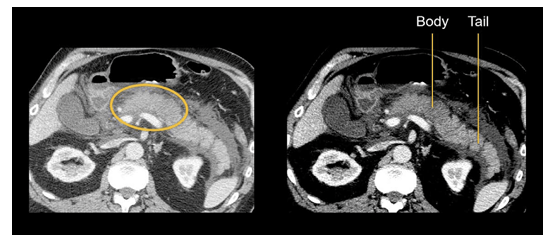

term image

-acute pancreatitis

-presence of focal or diffuse enlargement of the pancreas on CT or MRI